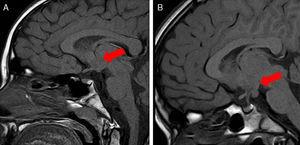

La causa más común de este padecimiento es un hamartoma hipotalámico (HH), que es un tipo de tumor, usualmente asintomático, en el hipotálamo. Los HH son tumores benignos compuestos por tejido ectópico neuronal y glial.

Imagen: Asociación Española de Pediatría